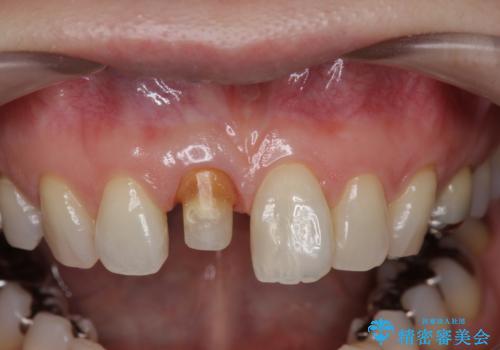

前歯の変色 セラミック審美補綴

- 前歯の変色の改善を希望され来院されました.

以前に神経が死に、根管治療を行った歯の変色が認められたためセラミックによる審美補綴治療を計画します。

神経治療を行い補綴(かぶせもの)治療を行わないと、変色が目立ち審美障害を起こすことがあります。

このような場合、セラミックによる審美改善が治療の一案として提案されます。